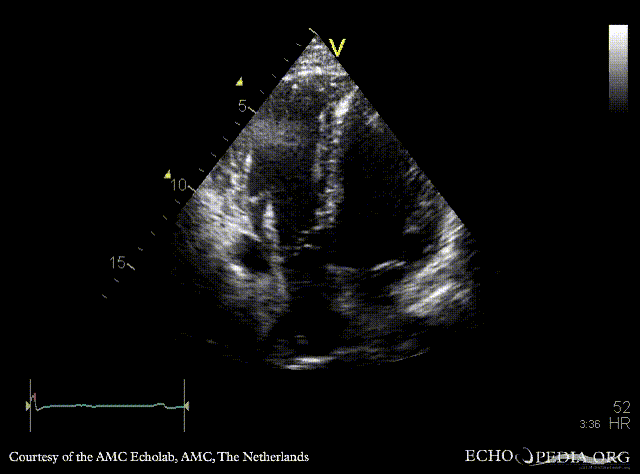

ARVD

PLAX: right ventricle dilatation in patient with ARVD PSAX: dilated right ventricle